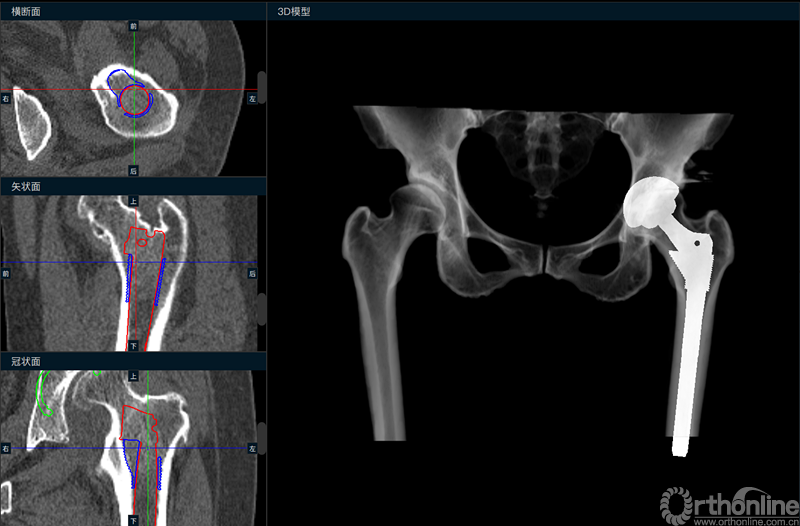

术前模拟术后X线片及假体位置轮廓线

根据规划结果,术前模拟得到术后X线片,并精确显示出髋臼杯、股骨柄假体在原有CT图像上的轮廓位置,以供术者进行参考。由于术前准备充分,手术过程开展顺利,仅60分钟即完成了手术,术后X线与规划一致,患者功能恢复良好,术后第二天即可下地行走。